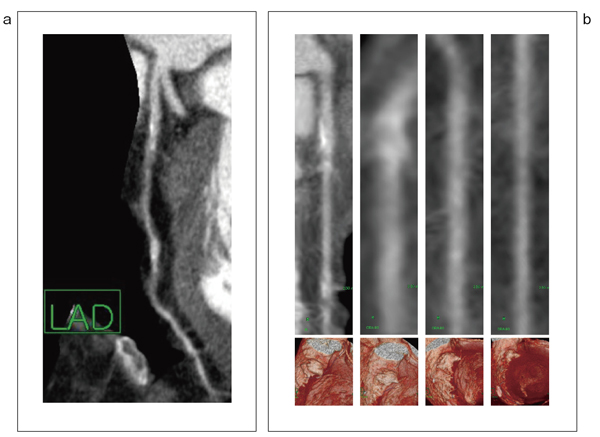

図3 頻脈症例における解析機能付き4D-sliding thin slab MIP法の有用性

a:最も画像ブレの少ない1時相を選ぶと,部分的に評価困難な画像ブレが含まれる。

b:画像ブレが多い血管(LAD)であったので,LAD1本を4時相(70%→10%→0%→40%)で解析を行った。4D法で解析することにより解析負荷も少なく,精度の高い読影につなげることも可能である。